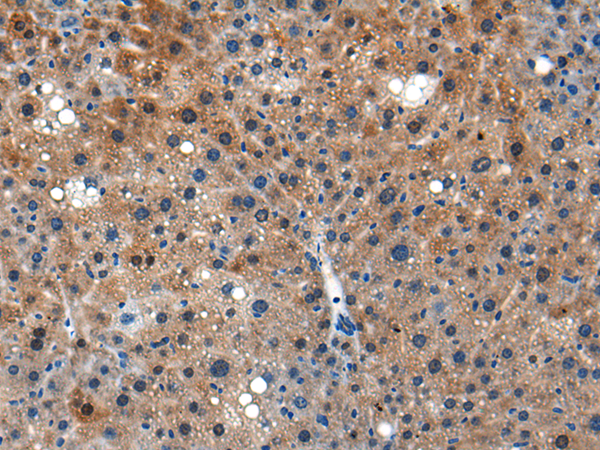

分类: 科研抗体货号: P04561别名:应用: IHC反应种属: Human, Mouse, Rat